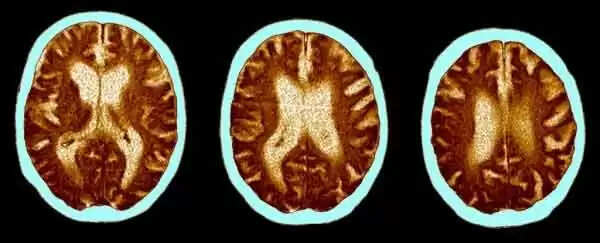

COVID-19 | കോവിഡ്-19: രോഗം ബാധിച്ചവരില് വൈജ്ഞാനിക വൈകല്യം; 20 വയസ് കൂടുതല് പ്രായമാകുന്നതിന് സമാനമായ ഗുരുതരമായ മസ്തിഷ്ക ആഘാതമെന്ന് പുതിയ പഠനം, 10 ഐക്യു പോയിന്റുകള് നഷ്ടമാകുന്നതിന് തുല്യം

ന്യൂഡെല്ഹി: (www.kvartha.com) കോവിഡ്-19 ബാധിച്ചവരില് ഗുരുതരമായ പ്രത്യാഘാതം. രോഗത്തിന്റെ അനന്തരഫലമായി 20 വയസ് കൂടുതല്

പ്രായമാകുന്നതിന് സമാനമായ ഗുരുതരമായ മസ്തിഷ്ക ആഘാതം ഉണ്ടാകുന്നുണ്ടെന്ന് യുകെയില് നടത്തിയ പുതിയ പഠനം. വൈജ്ഞാനിക വൈകല്യം 10 ഐക്യു പോയിന്റുകള് നഷ്ടമാകുന്നതിന് തുല്യമാണിതെന്നും ഗവേഷകര് പറയുന്നു. സാധാരണയായി, 50 തിനും 70 തിനും ഇടയില് പ്രായമുള്ളവരില് സംഭവിക്കുന്ന അവസ്ഥയാണിതെന്ന് ഇ ക്ലിനികല് മെഡിസിന് എന്ന ജേണലില് പ്രസിദ്ധീകരിച്ച പഠനം പറയുന്നു.